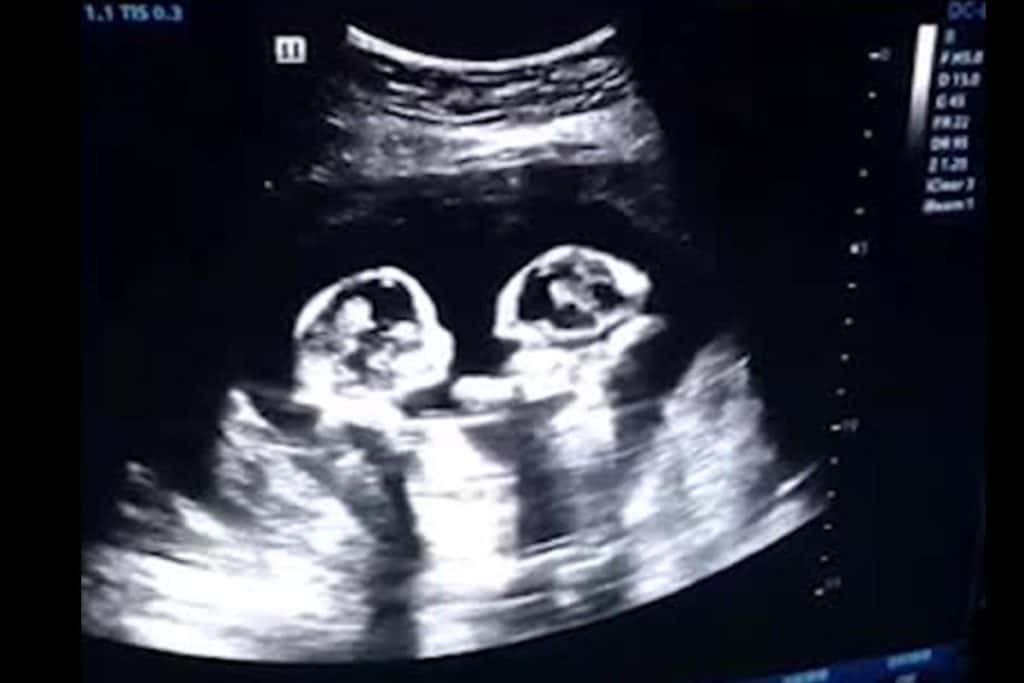

متى يظهر التوأم في كيس واحد داخل الرحم؟

تعتمد نتيجة عملية انجاب توأم على وقت انقسام البويضة بعد الإخصاب حيث أن انقسام البويضة في غضون 72 ساعة بعد الإخصاب، يؤدي إلى تكوين توأم من زوجين وكيس مائي منفصل في الموجات فوق الصوتية، لا يختلف هذان التوائم عن التوائم ثنائية البويضة يتم تخصيبها من بويضتين منفصلتين.

تسمى هذه الحالة ثنائية المشيمة / المشيمة السلوية المزدوجة إذا حدث الانقسام في اليوم الثالث إلى الثامن بعد الإخصاب، يتشكل التوأم في كيسين منفصلين من الماء ولكن مع زوج مشترك يفصل الغشاء الأمنيوسي الأكياس.

إذا كانت الأجنة في زوجين منفصلين، فإن سمك الجنين يكون أكبر مما هو عليه عندما يكون للأجنة زوج مشترك، وتسمى هذه الحالة المشيمة المزدوجة / المشيمية المزدوجة.

بشكل عام، زوجان منفصلان هما علامة على وجود توائم ملقحة حيث أن الحمل في توأم بزوج واحد يجعل من الصعب تشخيص المشيمة (عدد المشيمية أو الأغشية الخارجية التي تحيط بالجنين في حالات الحمل المتعددة) كما تلعب المشيمة عند التوائم دورًا مهمًا في نتائج الحمل.

في هذه الحالات، يكون سمك الغشاء بين الجنينين (يساوي أو أكبر من 2 مم) علامة على أن الجنين ثنائي المشيمة، في الأجنة أحادية البوريون، يكون الغشاء رقيقًا جدًا ولا يُرى عادةً حتى الثلث الثاني من الحمل.

استنادًا إلى المشيمة في الموجات فوق الصوتية عند 6-13 + 6 أسابيع، تظهر علامة الحمل الخاصة بنا في التوأم ثنائي المشيمة وتظهر علامة T في التوأم أحادي المشيمة، والذي يُطلق عليه أيضًا علامة الذروة المزدوجة (وهي نقطة البداية للغشاء) الانقسام على سطح المشيمة.